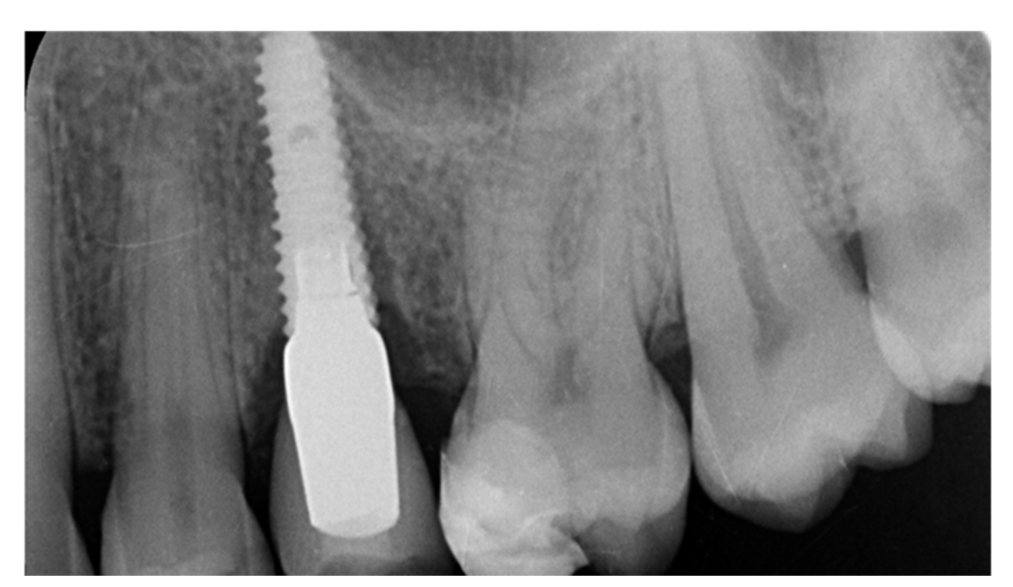

Implants fracture is an untreatable condition. There are several tools that may help clinician to remove the implant. However, fractured implant often presented damaged implant-abutment connection, hence, implant retrieval tools/kits (Figures 1–4) may not work. In cases implant is severely damaged and/or the residual osseointegration is very strong, such us in the mandible, the only possibility is to use a trephine burs (Figures 5–10).